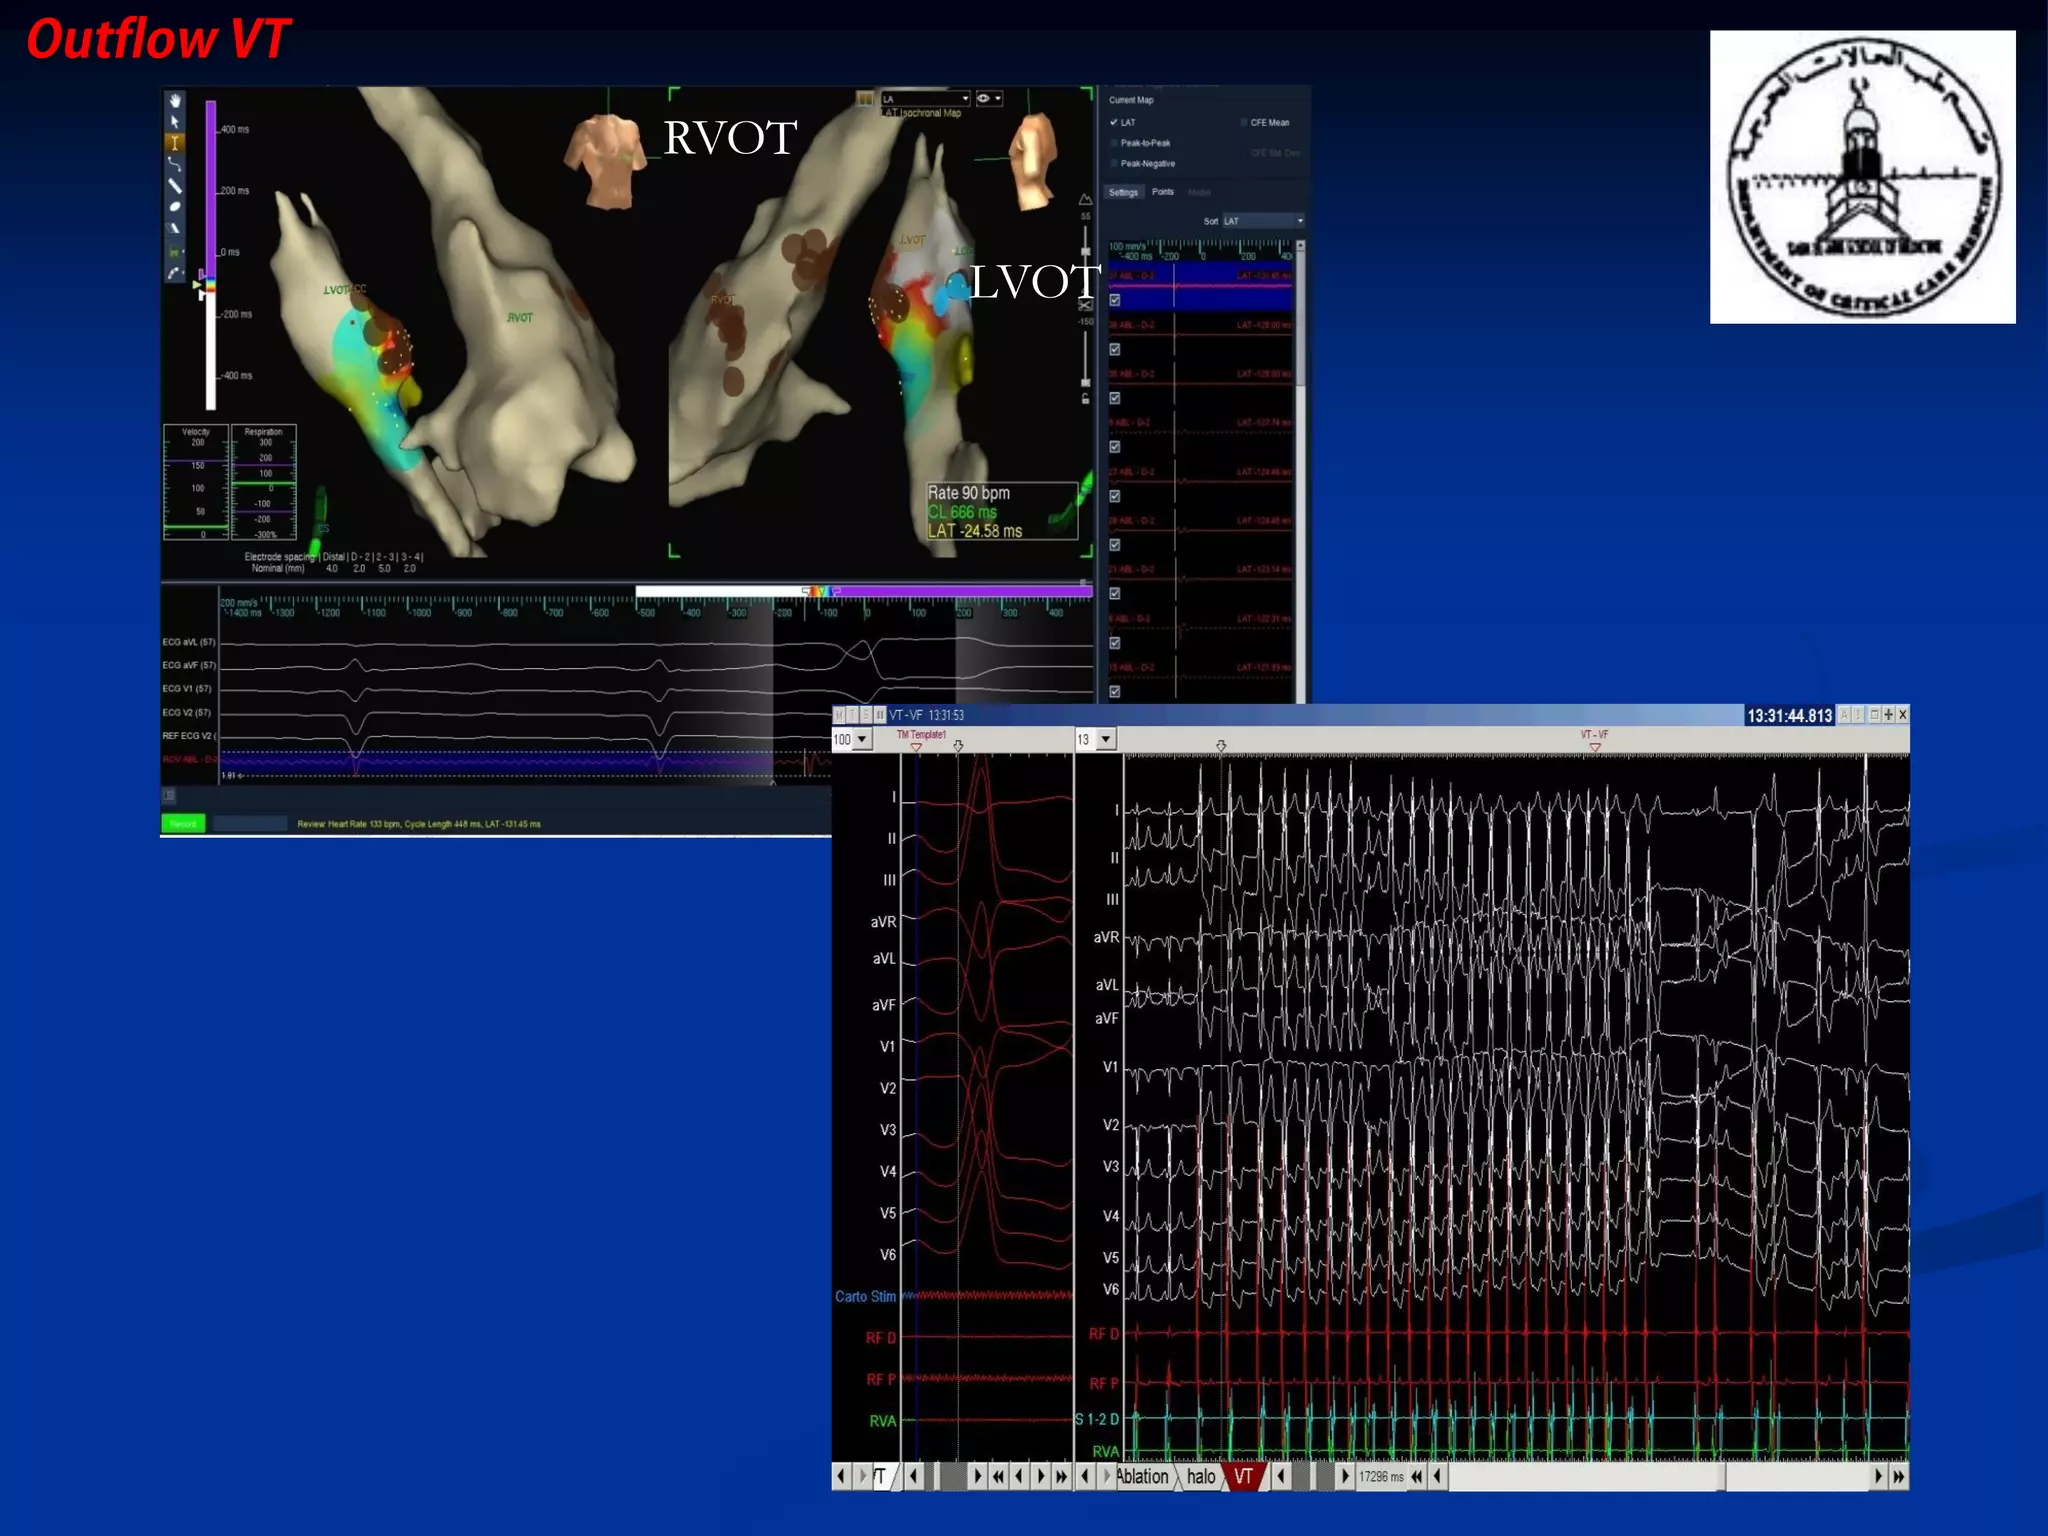

The document discusses various aspects of outflow tract ventricular tachycardia (VT) including its morphology, diagnostic tools, and the effectiveness of catheter ablation. It highlights the clinical characteristics necessary to distinguish malignant forms of right ventricular outflow tract (RVOT) VT, and the success rates and risks associated with radiofrequency catheter ablation. Additionally, it presents case studies illustrating the outcomes of such procedures in patients with idiopathic RVOT tachycardia.